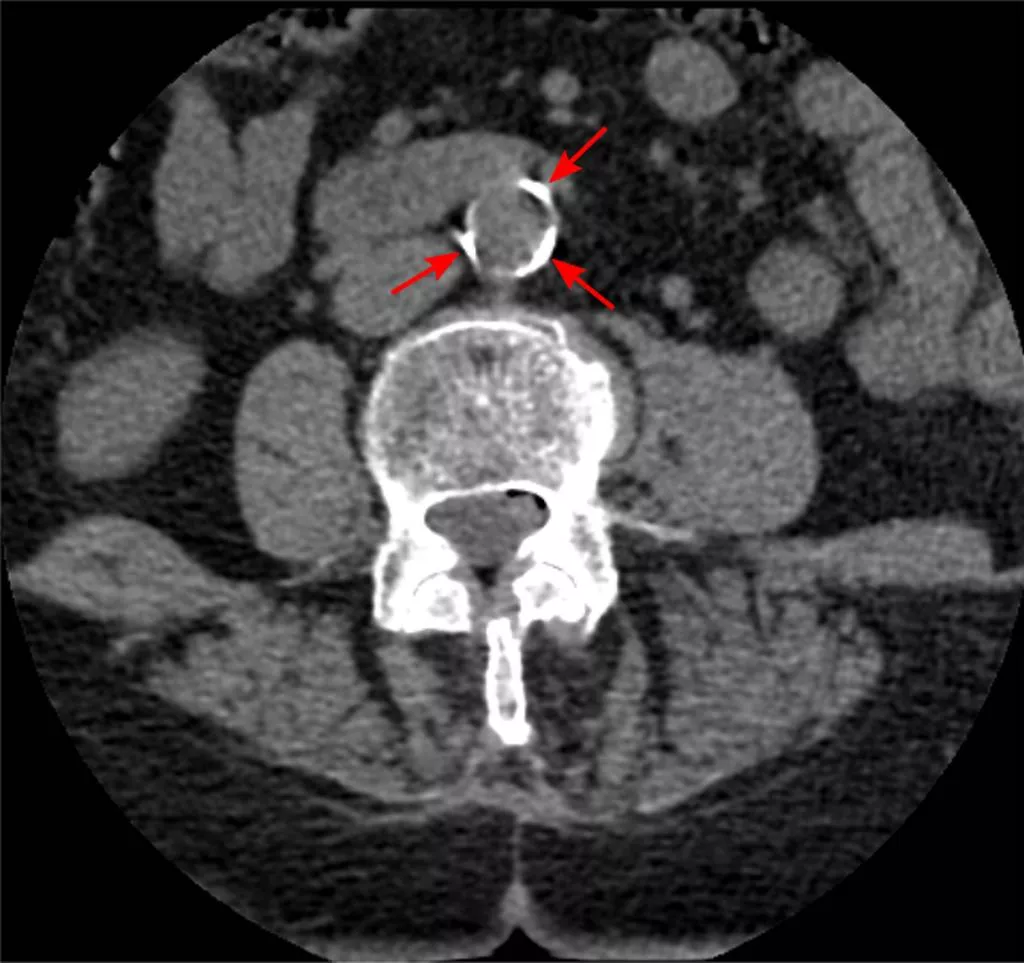

Érelmeszesedés Érelmeszesedés (aorta) Elmeszesedett hasi aorta CT rétegfelvételen. Forrás Jmarchn, liszensz: CC BY-SA 3.0 (Wikimedia Commons) Kategória Diagnosztika Közzétéve: 2020. 12. 09. 16:10 You must have JavaScript enabled to use this form. Saját név Hozzászólás A szövegformátumokról Egyszerű szöveg A HTML jelölők használata nem megengedett. A webcímek és e-mail címek automatikusan kattintható hivatkozásokká alakulnak. A sorokat és bekezdéseket a rendszer automatikusan felismeri. A mező üresen hagyandó